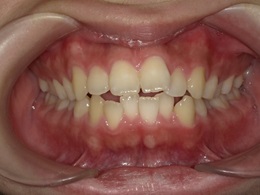

治療前正面

治療後正面